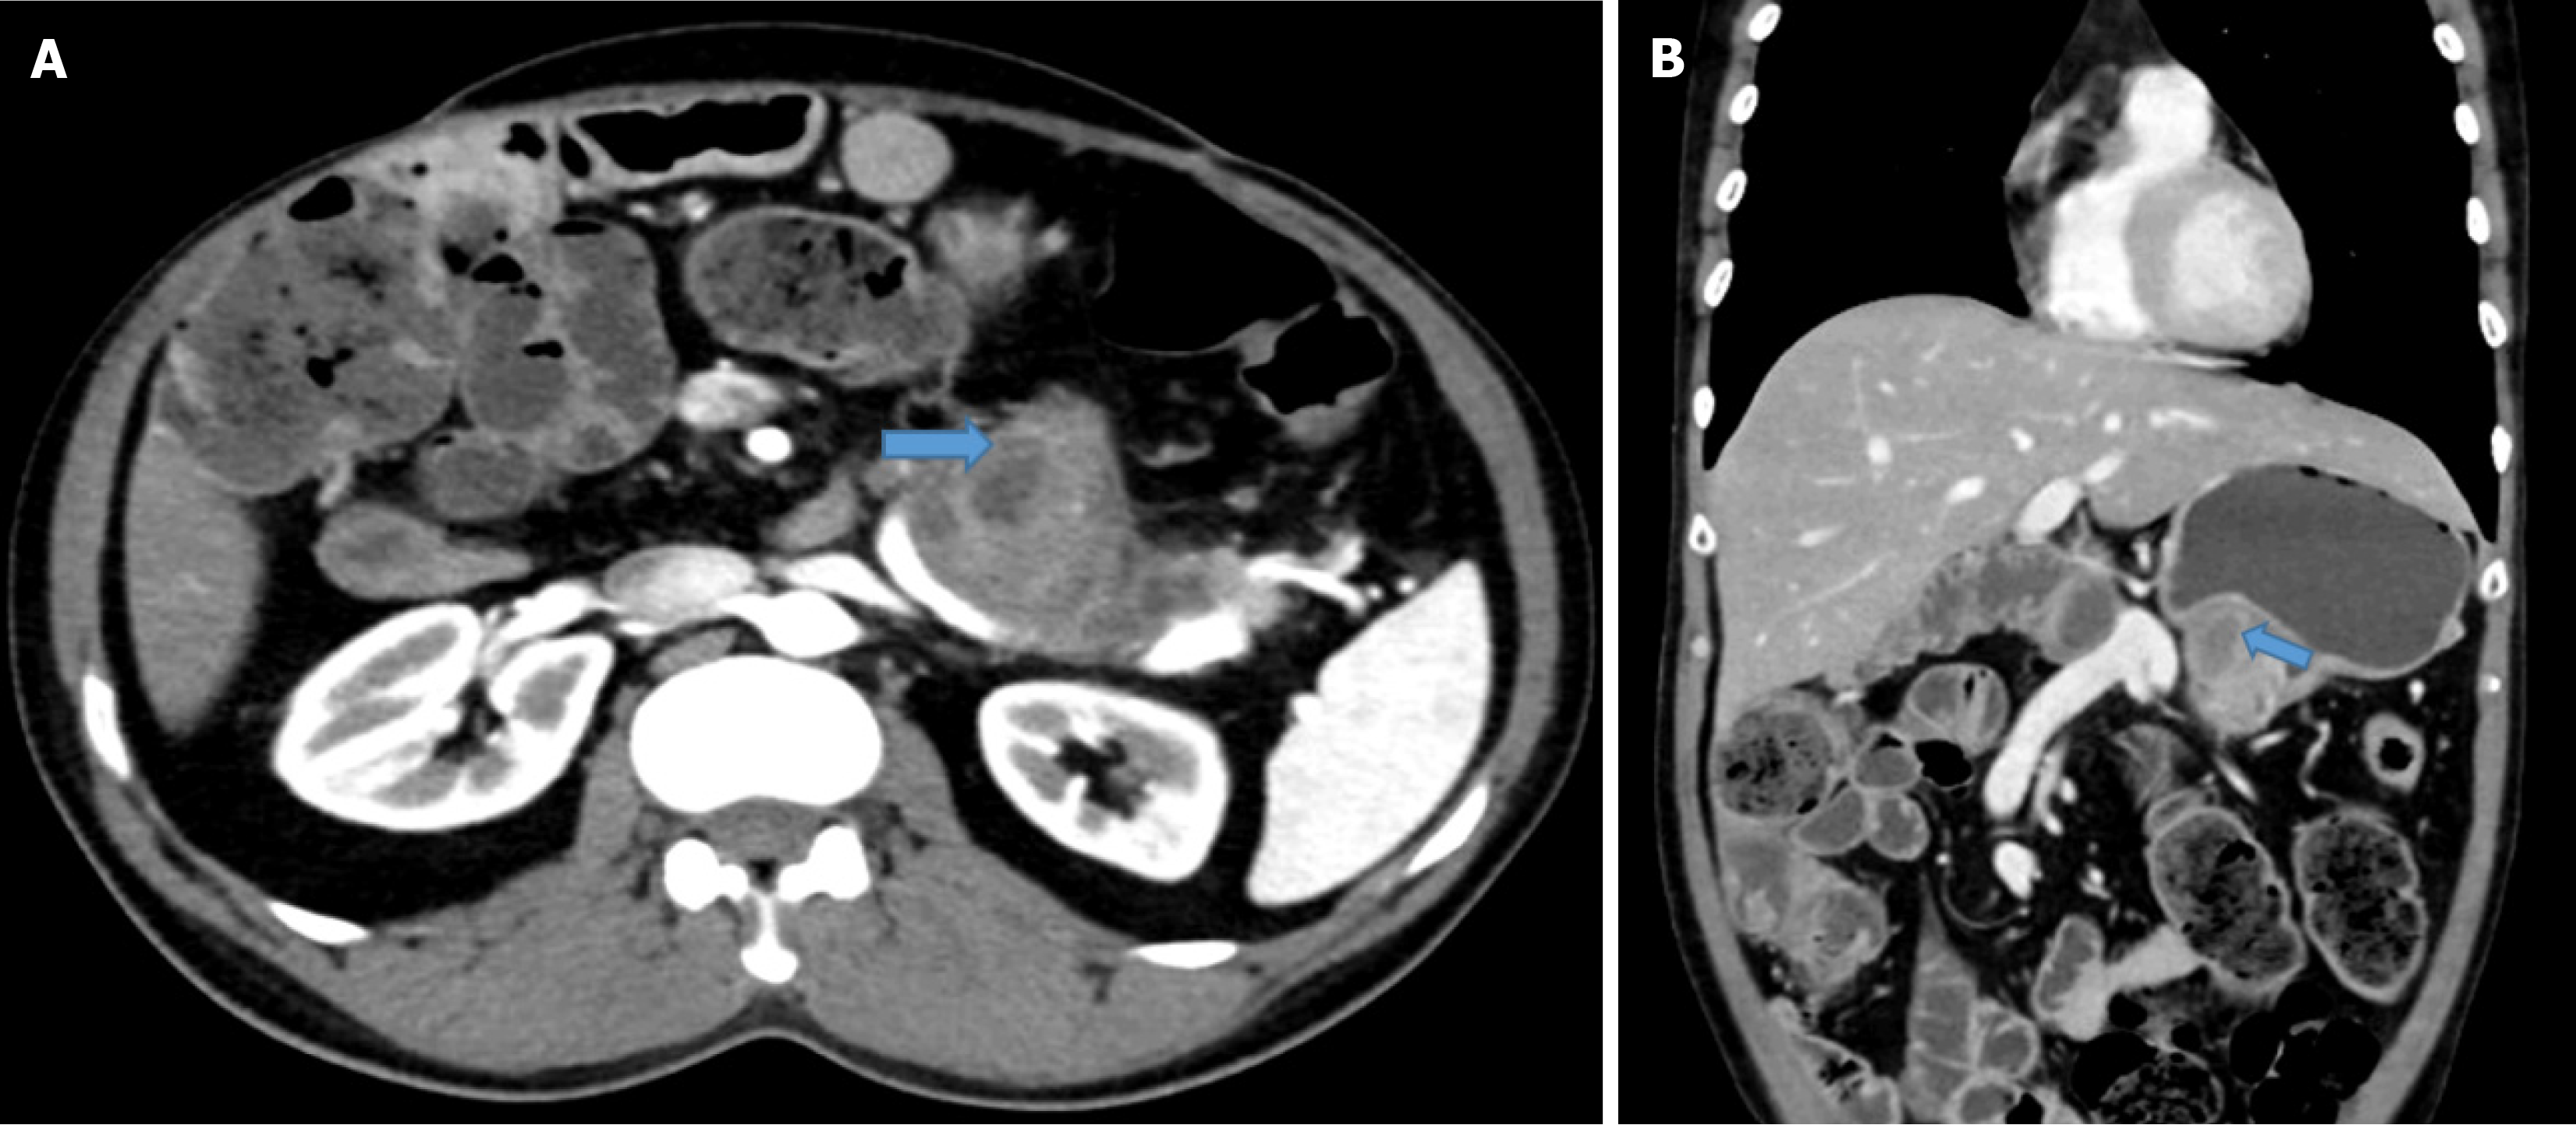

Clinically remnant pancreatic carcinoma presents with significant weight loss, exocrine insufficiency, abdominal pain, or back pain. In a few patients tumor markers, including carbohydrate antigen 19-9 or carcinoembryonic antigen, may be elevated. Hence, serial measurements in the follow-up period are essential for early diagnosis of recurrence. Contrast-enhanced CT and positron emission tomography with CT are crucial in evaluating recurrence and its extent. A representative image of contrast-enhanced CT showed a heterogeneously hypodense mass lesion measuring approximately 3.8 cm × 2.8 cm in the body and tail region involving the splenic vein (Figure 1). Endoscopic ultrasound with or without fine needle aspiration or endoscopic retrograde cholangiography cytology has also been used to confirm the diagnosis[21]. Moreover, previous surgical pathology, staging, and the time interval between index surgery and recurrence are important factors for planning further management. Usually, the interval between the index surgery and recurrence ranges from 6 months to 4 years. However, it can be seen even after 5 years.